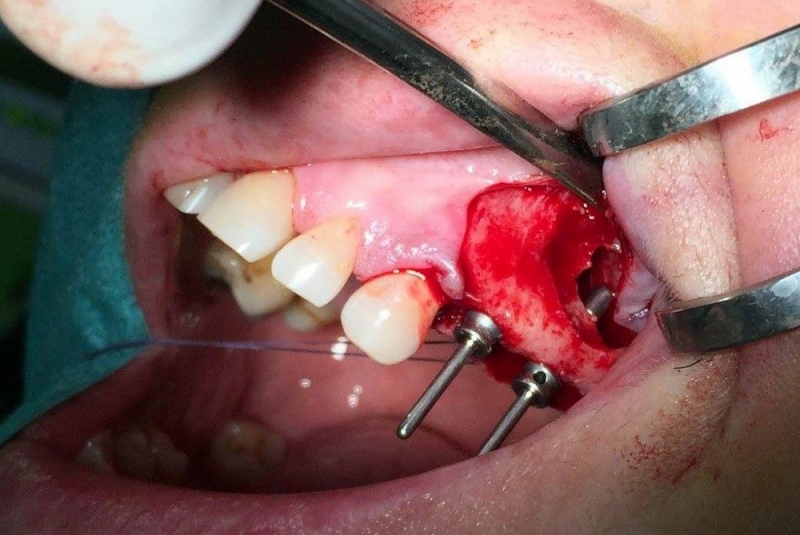

- Implantológia:

1. nadstavba kosti augmentačnými materiálmi (umelé kostné tkanivo, sinus lift a pod.)

2. implantológia, vrátane 3D - dentálneho CT